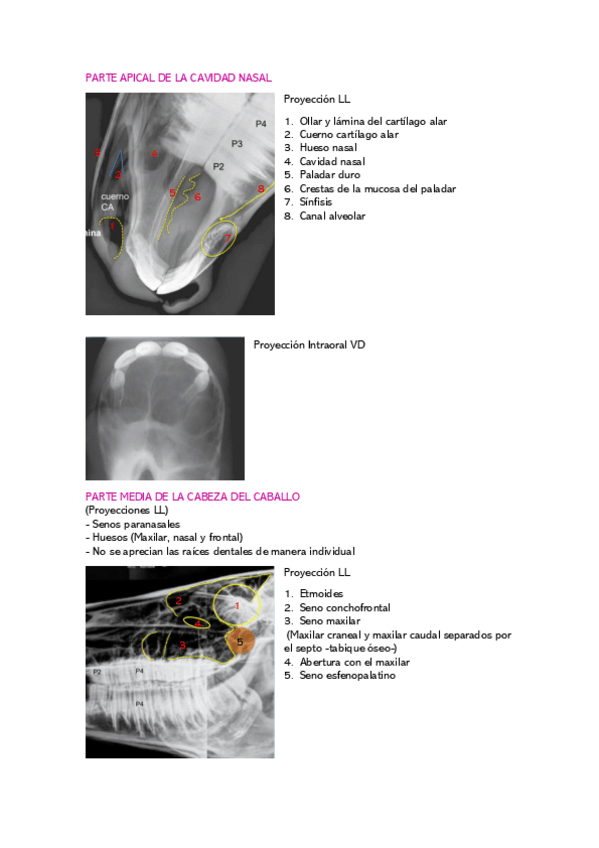

He publicado nuevos apuntes de 3º Diagnóstico Por Imagen: DXI-EQUIDOS.pdf

79 páginas